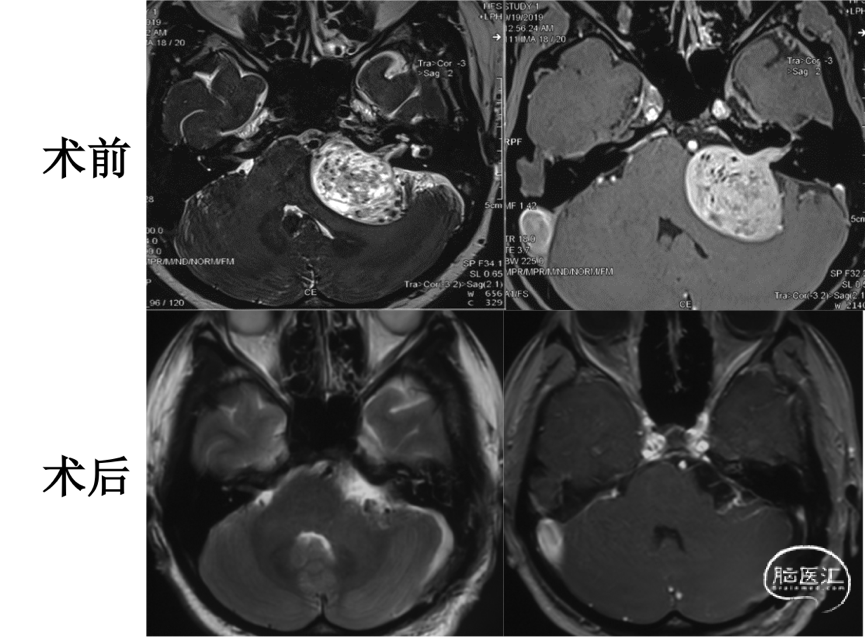

头颅MRI

术后复查

术后复查头颅MRI显示肿瘤全切,小脑无明显牵拉损伤。